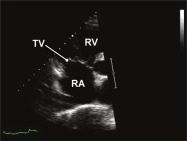

| 2.6. Mặt cắt trục dài cạnh ức qua buồng nhận thất phải |

||||||||

|

|

Cửa sổ siêu âm cạnh ức

Mặt cắt trục dài cạnh ức Ngả đầu dò xuống dưới hướng về phía đùi phải của bệnh nhân |

Nhĩ phải (RA) Van ba lá (TV) Thất phải (RV) |

|||||